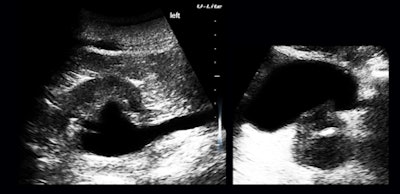

The clinic does not see pregnant women, but there were a few unexpected but very joyous first-trimester surprises (figure 4).

Vaginal bleeding seemed to be a pretty common presenting complaint, and even the first few cases included examples of the range of causes separable by ultrasound: polyps (figure 5a), endometrial hyperplasia, and adenomyosis.

The polyp case was a woman with a three-year history and no diagnosis. The adenomyosis patient had heavier bleeding for almost the same length of time and was deathly pale when she presented during a clinic "ultrasound day"; anemia did not seem to have been a clinical consideration. The endometrium was reduced to a thin, denuded basal layer in another woman with a month of bloody flow (figure 5b).

I am including this case because it reminded me of a clinical pearl: Whenever you have vaginal bleeding without an ultrasonically visible cause, think of clotting disorders such as von Willebrand disease.